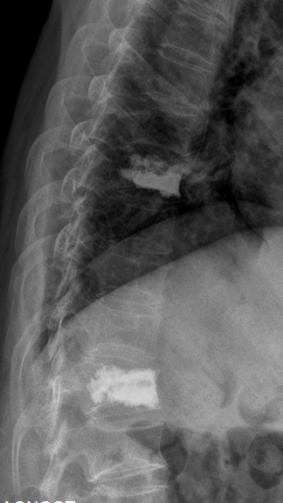

术前核磁共振检查明确T8.12椎体骨折,为疼痛责任椎体;经皮穿刺微创椎体成形术后复查可见椎体高度恢复良好,骨水泥弥散满意。

自2019年我院创伤外科“精细化椎体成形治疗老年骨质疏松性压缩骨折”获得广州市临床特色项目以来,在医院的大力支持下,刘志祥主任团队追求卓越的步伐从未歇息,对此项技术的检查方法及手术技巧进行了进一步的钻研,以更熟练的技术和更小的创伤为更多的老年性骨质疏松椎体骨折患者解除痛苦。通过术前过伸位X线检查,为无MRI设备基层医院或身体原因无法行MRI检查患者,提供新的检查手段,以便早期诊断、早期治疗。术前对伤椎3D打印模型仔细研究,模拟穿刺方向、深度等,根据不同患者骨折类型,制定个性化穿刺路径,减少穿刺损伤风险和手术时间等,有效减轻疼痛和快速康复。正如刘志祥主任期待,老年骨质疏松性患者能够得到更科学、更微创、更规范的治疗,有效解决疼痛,恢复日常生活,并有效避免再次骨折。

术前过伸位X、CT检查,早期诊断